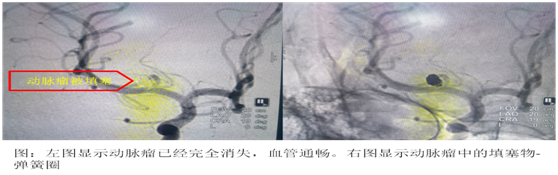

患者很年轻,我们尽快安排了介入手术,脑血管造影结果明确了出血的原因,右侧大脑中动脉瘤。

我们正确选择微创介入治疗,不需要开颅,尽可能的减少患者的副损伤,手术顺利,动脉瘤完全填塞,术后复查头颅CT,患者没有再出血。